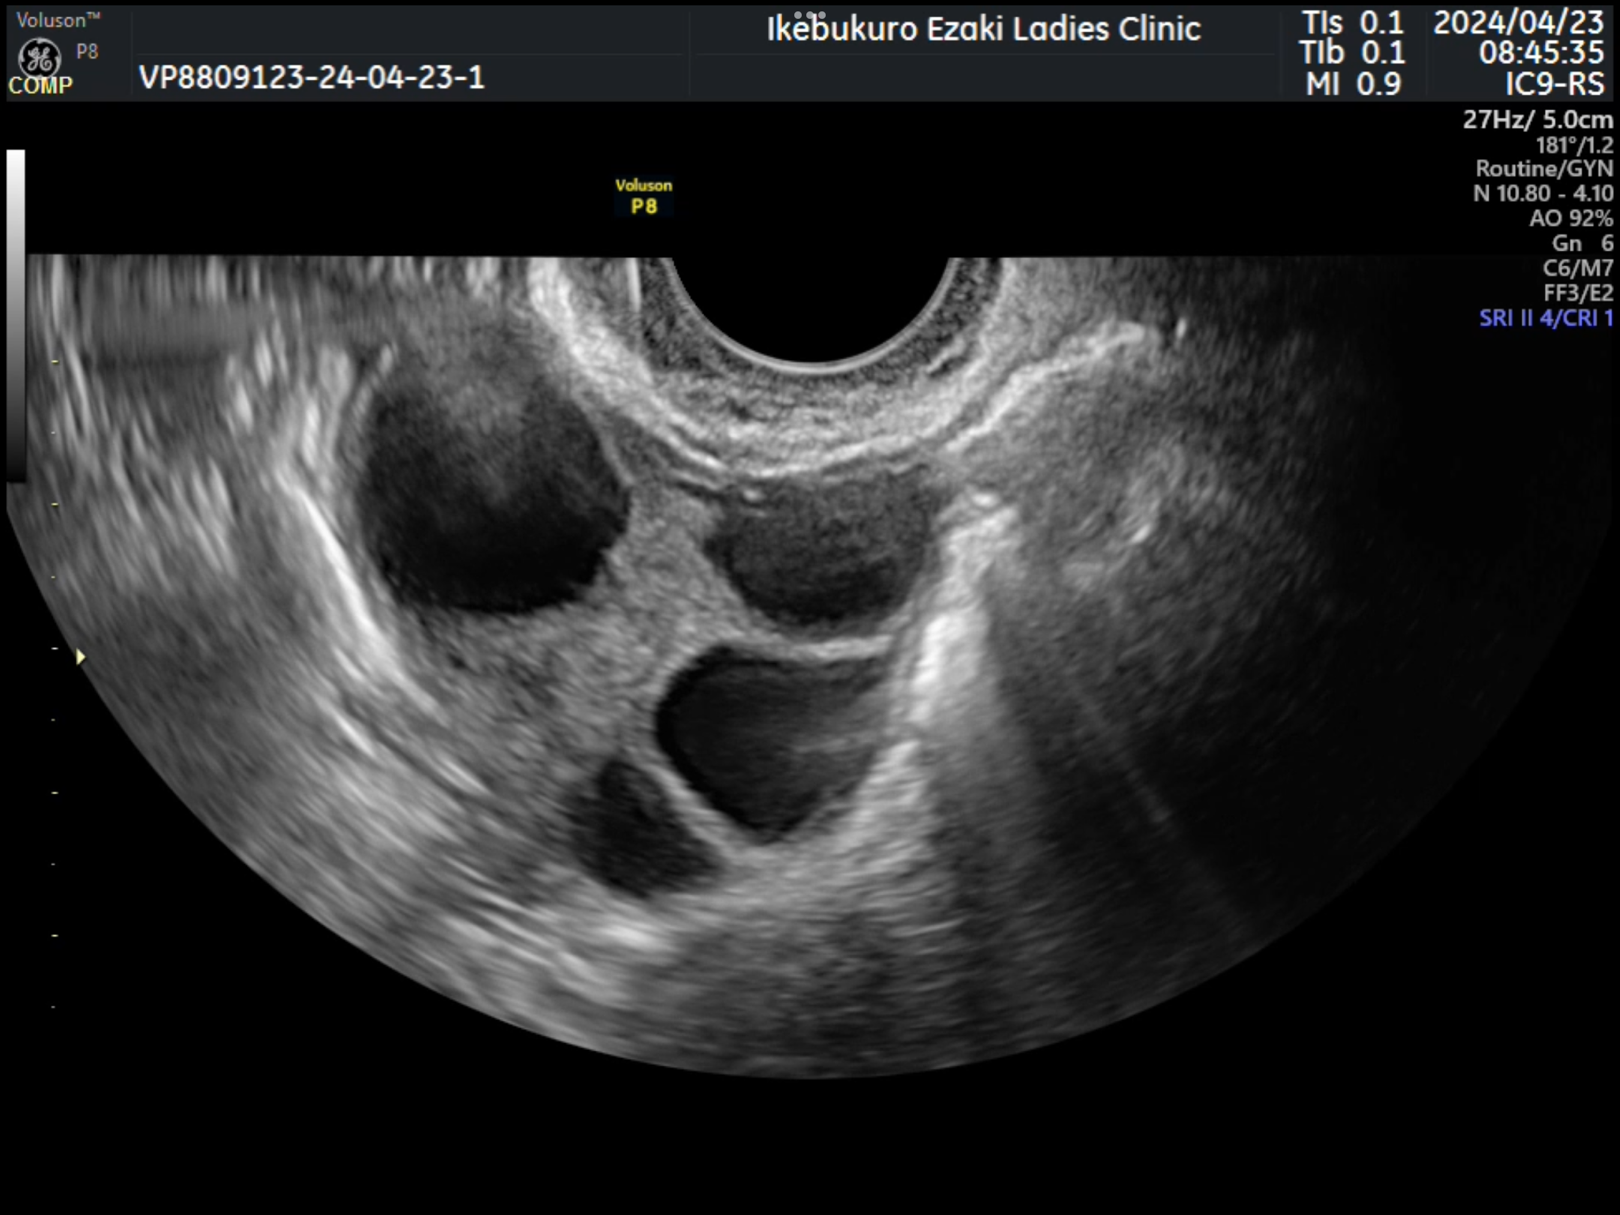

当院では通常のX線の卵管造影検査ではなく「超音波下卵管造影」という方法を行います。

X線やアレルギーの多い造影剤を使用しないため被爆の危険もなく副作用が少ないことが特徴です。

アレルギーの多い造影剤でなく生理食塩水を用いるのでアレルギーなどの副作用が起こりにくいという長所があります。生理食塩水を注入するため造影剤よりも痛みを少なくすることが可能となります。